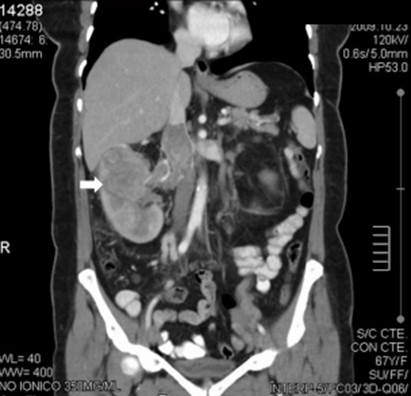

La Categoría IIF exhibe múltiples septos finos en su interior, realce evidente en paredes o septos, mínimo grado de engrosamiento de la pared, calcificación grosera o nodular, lesiones intra renales densas sin realce o con realce de septos o pared, siendo este realce no medible en las lesiones descubiertas con incremento de la densidad radiológica cuando se comparan las imágenes sin y con contraste yodado IV. Se consideran masas quísticas moderadamente complicadas y precisan seguimiento con controles cada seis meses.(19, 20) No requieren tratamiento quirúrgico inmediato y el riesgo de evolucionar a quistes malignos es del 5%, quistes con aspecto hiperdenso > 3 cm (Anexos 7 y 8).

La Categoría III muestra engrosamientos lisos o irregulares de la pared o de los septos intra quísticos y existencia de realce medible en TC y RMI. Se consideran masas indeterminadas y precisan de primera instancia cirugía, nefrectomía parcial o ablación por radiofrecuencia, salvo contraindicaciones clínicas.(19, 21) Aproximadamente el 40%-60% son lesiones malignas (carcinomas renal quístico), siendo el restante benignas, que incluyen quistes hemorrágicos, infectados crónicos o calcificaciones parietales, nefrona quístico multiloculado, quistes multilobulados, quistes con tabiques complejos, etc. (Anexos 9 y 10).